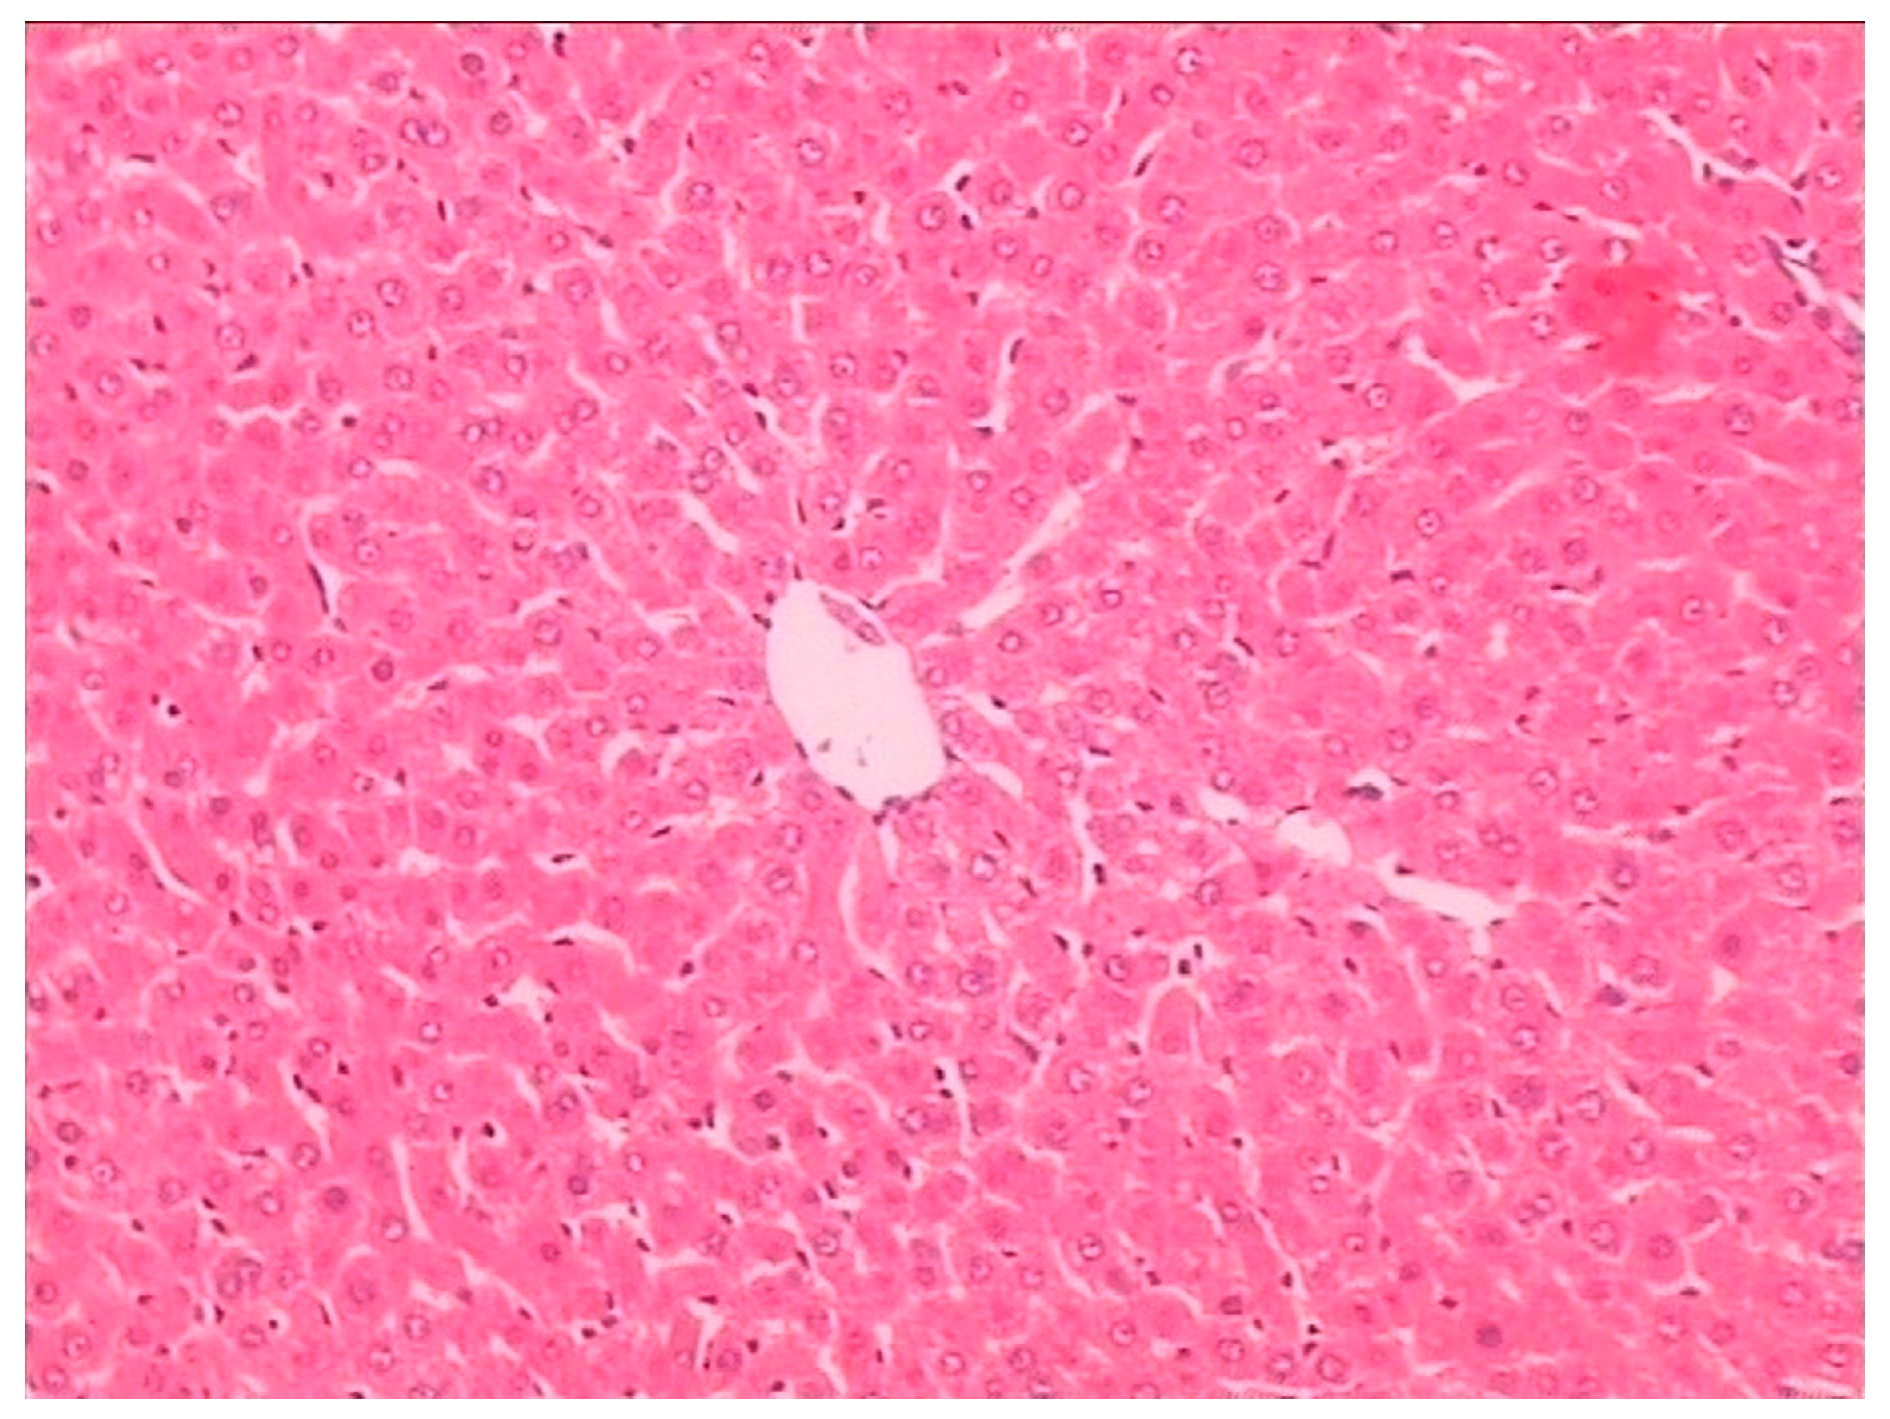

2.3. Histopathological Examination

Histopathological examination showed there was severe toxic damage occurring in the GE group, and no injuries were observed in the MG group at the same dose of 0.72 mmol/kg. In the MG group, the livers were soft, ruddy, and shiny, with normal shape and size. There was no swelling degeneration of liver cells, or expansion of the central vein and bile duct hyperplasia in the MG group. In contrast, cell swelling degeneration, expansion of the central vein, bile duct hyperplasia, and inflammatory infiltrate were observed in the GE group. A widening of the intercellular space became wider and focal cell necrosis were also observed to occur in the GE group (Figure 2, Figure 3 and Figure 4).

Figure 2.

Hematoxylin and eosin (HE)-stained histological sections of rat liver in the control group (Magnification: ×400).